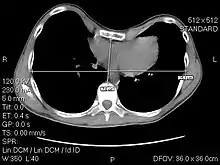

The Haller index, created in 1987 by J. Alex Haller, S. S. Kramer, and S. A. Lietman,[1] is a mathematical relationship that exists in a human chest section observed with a CT scan. It is defined as the ratio of the transverse diameter (the horizontal distance of the inside of the ribcage) and the anteroposterior diameter (the shortest distance between the vertebrae and sternum).[2]

where:

- HI is the Haller Index

- distance 1 is the distance of the inside ribcage (at the level of maximum deformity or at the lower third of the sternum)

- distance 2 is the distance between the sternal notch and vertebrae.